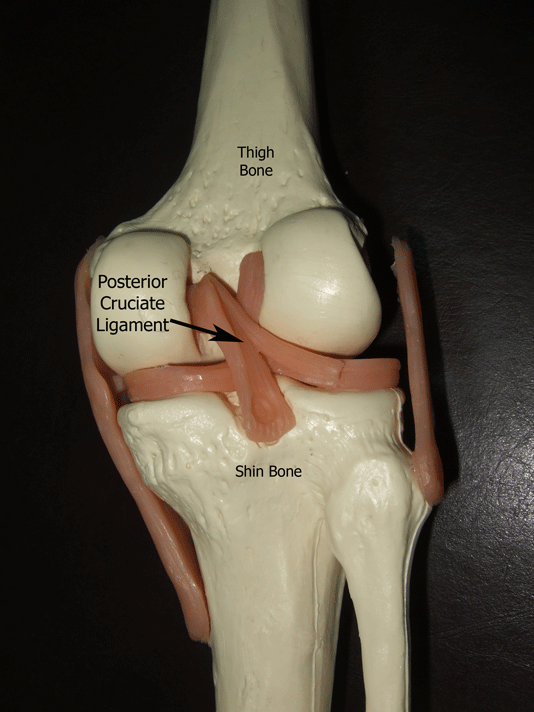

A ligament is a strong fibrous tissue that attaches one bone to another.

The anterior and posterior cruciate ligaments form an “X” in the centre of the knee joint. The posterior cruciate ligament (PCL) being the larger of the 2 and situated behind the anterior cruciate ligament (ACL).